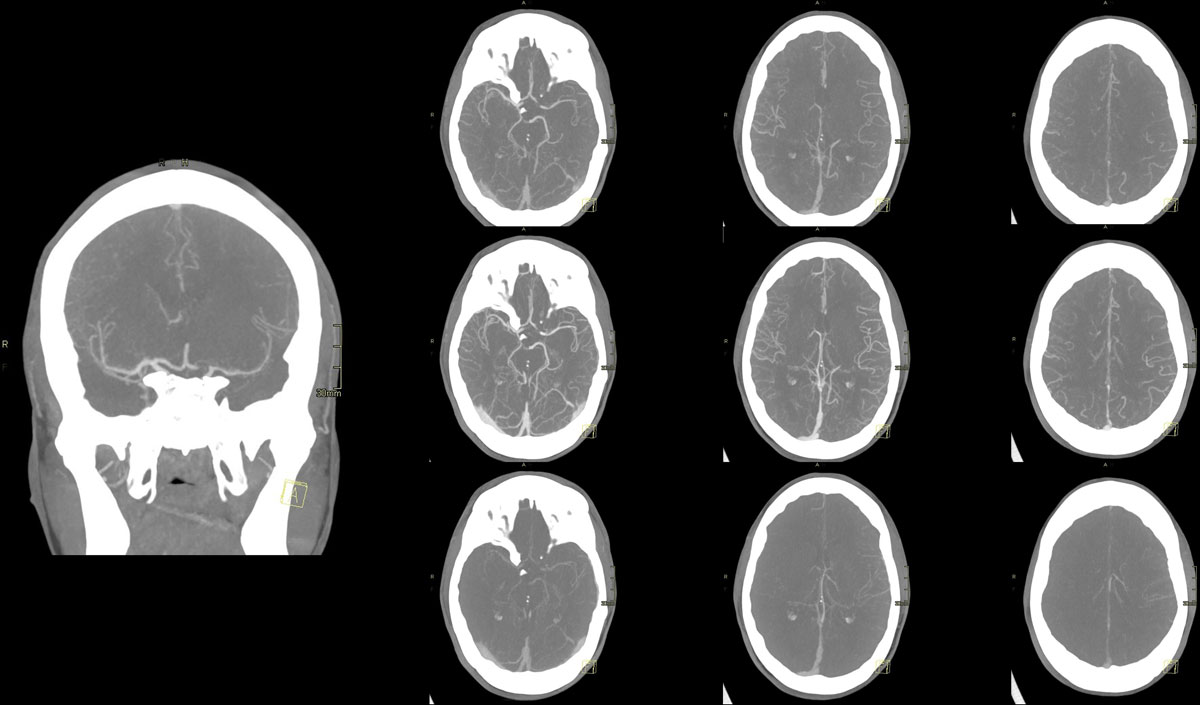

This clinical case presents a 28-year-old female patient presenting with a wake-up stroke, managed with endovascular treatment.

CT – CTA - CTP

24h CT-scan

24h CTA and CTP